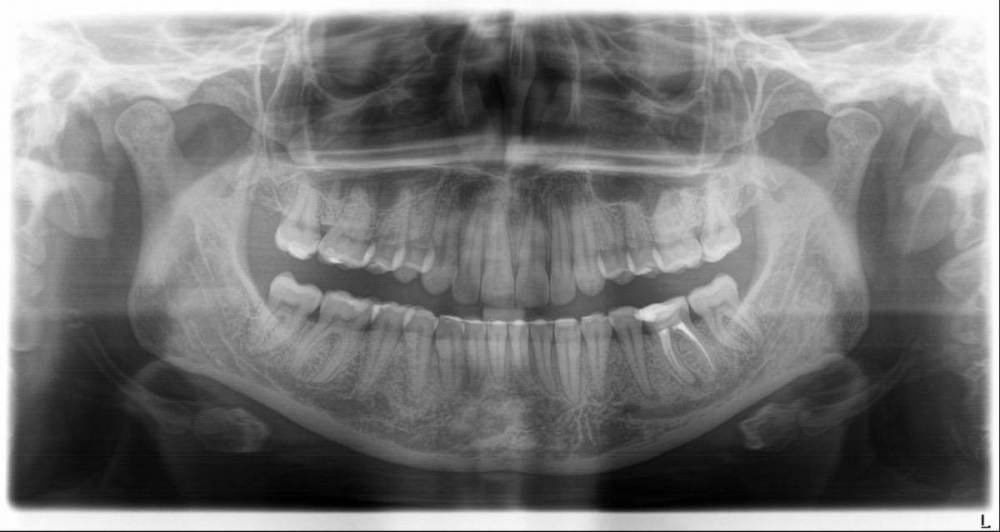

IvanK Опубликовано 24 марта, 2023 Поделиться Опубликовано 24 марта, 2023 Здравствуйте Выложите фото зуба на ОПТГ бросается в глаза зуб 3.6 Ссылка на комментарий